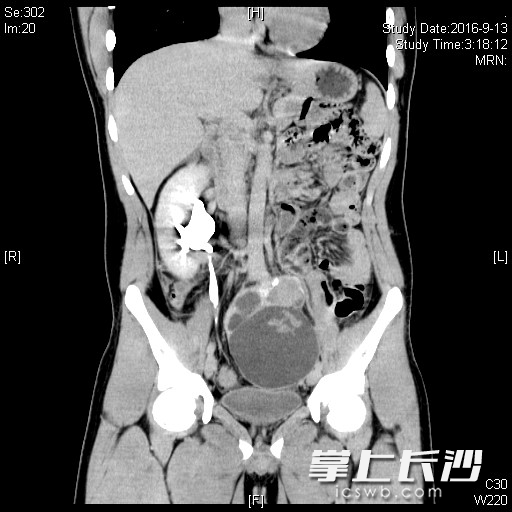

ct显示,王亮(化名)的左肾不见了。

王亮被腹痛的毛病困扰了4年,反复发作,最近因疼痛加剧入院。ct显示,王亮的左肾并不在他左侧腰部,而是跑进了盆腔。“现在这个藏起来的肾出现重度积水,破裂出血,病情严重,需尽快手术。”医生为王亮量身定制了手术方案,仅通过3个微创切口,在腹腔镜下完成手术。由于异位的左肾与正常肾脏形状相差较大,又与结肠、膀胱、大血管相邻,极易损伤到周围脏器和血管,手术难度大,专家团队耗时120分钟顺利完成手术。下午,王亮就能下床活动,肚子也不痛了,预计5天即可康复出院。